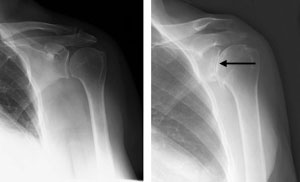

Osteoarthritis of the shoulder.

(Left) An x-ray of a healthy shoulder joint. (Right)Osteoarthritis of the shoulder. Note the the decreased joint space in the x-ray (arrow).

(Left) Rotator cuff arthropathy. (Right) The reverse total shoulder replacement allows other muscles — such as the deltoid — to do the work of the damaged rotator cuff tendons.